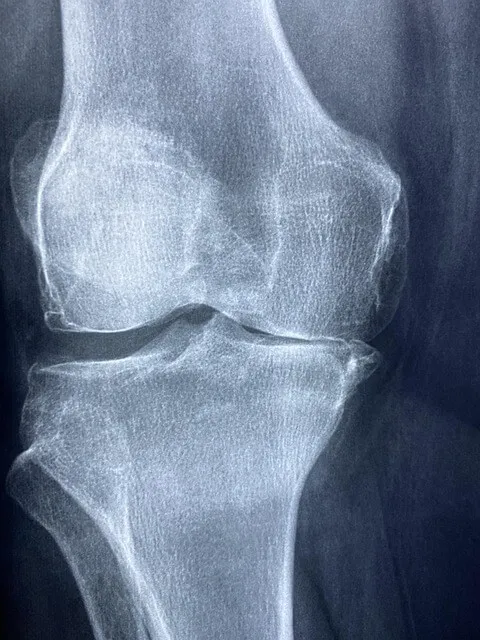

- X-ray 또는 MRI에서 연골 연화가 관찰되는 경우

- 전문의 진료 및 진단 검사 (X-ray, MRI 등)